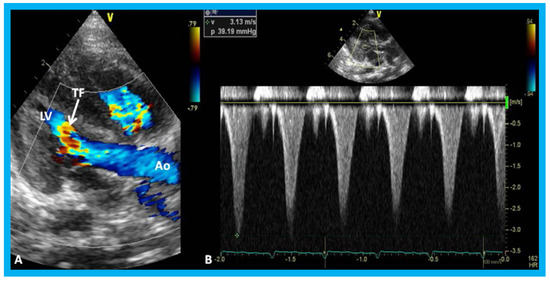

Figure 20. (A) Selected video frame from a subcostal four chamber view (similar to Figure 19B) with color-Doppler demonstrating turbulent flow (TF) in the pulmonary outflow tract. (B) Continuous wave Doppler recording across the pulmonary outflow tract demonstrates peak Doppler velocity of approximately 5 m/sec suggesting significant obstruction. MLV, morphological left ventricle. Reproduced from Yarrabolu T.R., et al. [23].